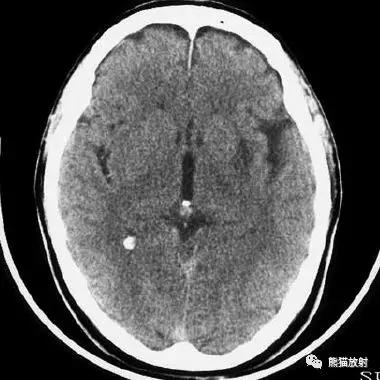

左侧尾状核头脑梗死;右侧外囊腔隙性脑梗死。